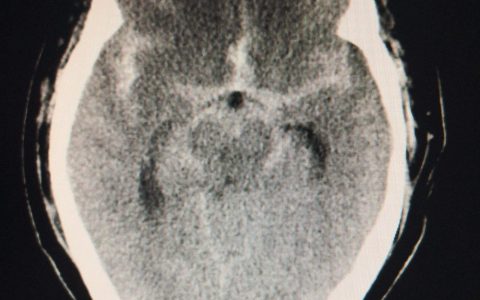

除多导睡眠描记术外,上述所有检查均可用于识别双侧膈肌麻痹——当患者在呼吸过程中出现反常腹部运动时,应考虑这一诊断。在该病例中,吸气和呼气期间获得的胸片显示两侧膈肌运动不足。肺量测定还发现,当患者从直立位移动到仰卧位时,用力肺活量减少50%以上。膈肌麻痹的潜在原因包括影响神经系统、肌肉本身或神经肌肉接头的过程。该患者的颈椎磁共振成像显示C3至C6椎管狭窄并伴有骨髓炎。患者开始接受夜间持续气道正压通气,并被转诊接受进一步评估。